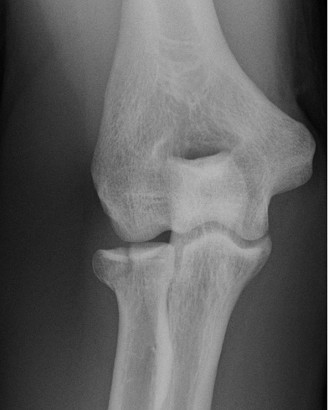

Standard orthogonal radiographs (anteroposterior and lateral) provide a baseline assessment of joint congruity, hardware position, and the gross extent of heterotopic ossification. However, a high-resolution Computed Tomography scan with three-dimensional reconstructions is the gold standard and an absolute requirement. The 3D CT scan allows the surgeon to precisely map the location of the heterotopic bone, distinguishing between extra-articular bridging bone and intra-articular osseous blocks. In our patient, the CT scan would explicitly define the posterior-medial mass and its relationship to the cubital tunnel and the medial column hardware.

Active and passive range of motion measurements were performed, demonstrating severe limitations. The flexion-extension arc was from 70 degrees of extension deficit to 105 degrees of flexion. This represents a severely restricted arc of 35 degrees. Both extension and flexion had a hard, bony end-feel. Forearm rotation was also compromised, with pronation limited to 45 degrees and supination limited to 30 degrees. These limitations were likely secondary to capsular and soft tissue contracture, as well as the radial head excision and subsequent radioulnar scarring.

Palpation revealed a firm, non-tender mass along the posterior-medial aspect of the elbow, extending from the distal humerus to the proximal ulna, suggestive of heterotopic ossification. Tenderness was elicited over the medial and lateral epicondyles with deep palpation. The ulnar nerve groove felt thickened and somewhat immobile at the cubital tunnel. There was no palpable joint effusion. The surgical hardware appeared well-seated, with no signs of prominence or superficial irritation.

In the clinical vignette presented, the patient exhibits classic risk factors for profound post-traumatic stiffness and heterotopic ossification, including a high-energy mechanism, comminuted intra-articular fractures requiring extensive surgical exposure, delayed mobilization (three weeks of immobilization), and radial head excision. The presence of a hard, bony end-feel combined with ulnar neuropathy strongly suggests that the heterotopic bone has bridged the ulnohumeral articulation and encroached upon the cubital tunnel.